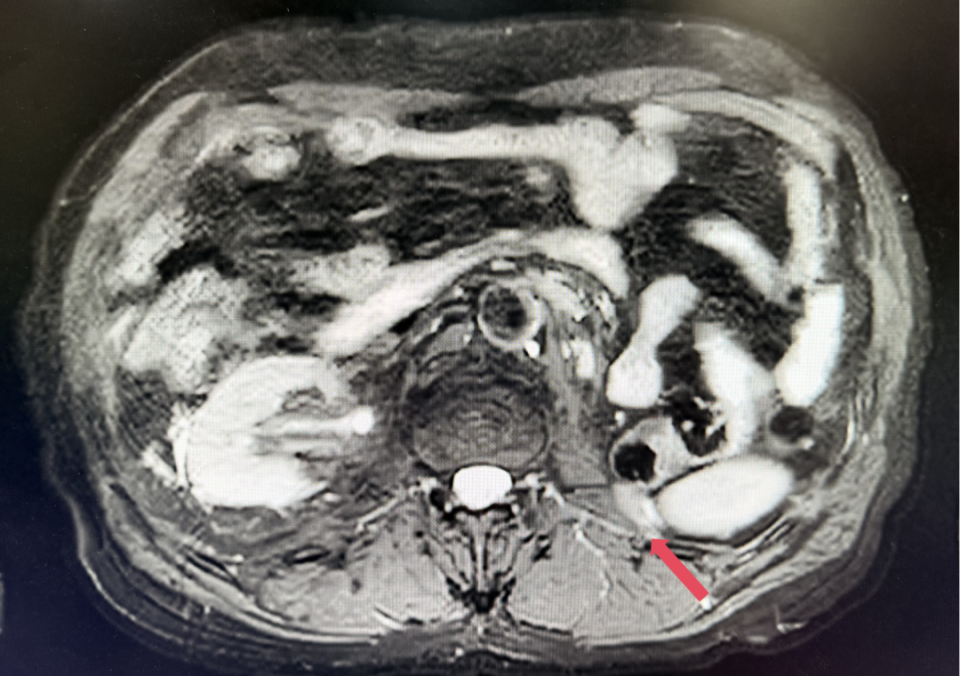

2023年3月,初始应答

2023年3月:用药6周(C2)后首次肿评,肿瘤负荷减少至76.8mm,达到PR。

患者初诊时68岁,2020年9月因“体检发现左肾占位2年”行腹腔镜下左肾根治性切除术,术后病理提示为肾透明细胞癌,pT3aN0M0,未行术后辅助治疗、未规律复查。2022年3月胸腹盆CT示腹膜后转移,IMDC评分0分,低危组。随后予一线培唑帕尼治疗,最佳疗效SD,2022年11月PD。于2023年1月经筛选进入Ⅲ期FRUSICA-2临床研究,开始接受呋喹替尼联合信迪利单抗二线治疗,用药6周(C2)后首次肿评即实现疗效PR(缩瘤率40.2%),用药10个月时缩瘤率近七成(68%),并维持上述水平至今,PFS已经超过37个月,在二线治疗中实现了长期无进展生存。同时,患者对呋喹替尼联合信迪利单抗方案耐受性良好,仅见轻微蛋白尿和偶然腹泻,未见其他不良反应,也未见免疫治疗相关不良反应。该方案有望为TKI经治的晚期肾癌患者带来新的选择,为实现长期生存提供可能性。